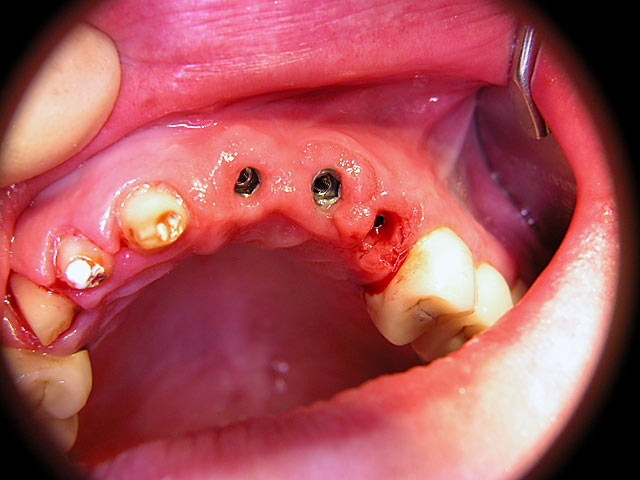

Kurzimplantate und Sofort – Implantate: